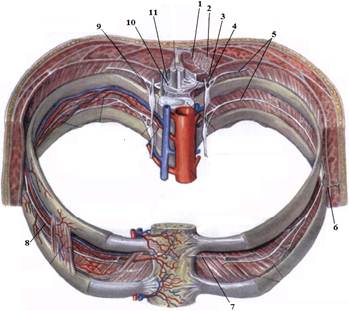

ТЕМА: Грудні нерви, розподіл дорсальних (задніх) гілок. Яремний, підключичний і бронхосередостінний стовбури. Міжреброві нерви, хід, топографія, ділянки іннервації. Судинно-нервовий пучок міжребрового проміжку.

е) склад та топографію судинно-нервового пучка міжребрового проміжку.

7. Судинно-нервовий пучок міжреберного проміжку.

На таблицях і трупах студенти знаходять судинно-нервового пучка міжребрового проміжку. Далі на трупі розглядають хід і розподіл грудних нервів та ділянки їх інервації, Користуючись таблицями вивчають лімфатичні судини і вузли грудної клітки. На трупі ззаду і справа від грудної аорти знаходять грудну протоку. Визначають її корені хід топографію. На таблицях вивчають корені правої лімфатичної протоки визначають ділянки відпливу до двох головних лімфатичних проток.Викладач консультує студентів по темі заняття, показує незрозумілі деталі будови. В кінці заняття викладач шляхом тестування кінцевого рівня знань та вмінь оцінює роботу кожного студента в академічному журналі.

1. Яким номером позначено N. thoracicus?

2. Яким номером позначено N. intercostalis?

3. Яким номером позначено R. cutaneus lateralis?

4. Яким номером позначено R. dorsalis n. thoracici?

5. Яким номером позначено R. cutaneus lateralis r.dorsalis n. thoracici?

6. Яким номером позначено R. cutaneus medialis r.dorsalis n. thoracici?

7. Яким номером позначено R. cutaneus anterior?

8. Яким номером позначено Rr.communicantes n. thoracici?

9. Яким номером позначено Radix dorsalis n. thoracici?

10. Яким номером позначено Radix ventralis n. thoracici?